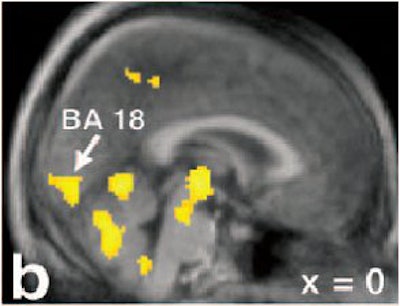

![]() ![]() |

Activations are superimposed on the averaged MRI of the volunteers. Activation in the secondary visual cortex (b, BA 18) and the posterior cingulate/precuneus (c, BA 23/31) can be found. Note in sections a-c that the activation in the mesodiencephalic transition zone (mes-di) extends from the rostral midbrain into the ventral parts of the caudal thalamus x = 12 mm left to the intercommissural line. Holstege G, Georgiadis JR, Paans AM, Meiners LC, van der Graaf FH, Reinders AA, "Brain activation during human male ejaculation," J Neurosci 2003 Oct 8:23(27):9185-93. Copyright 2003 by the Society for Neuroscience.

Finally, "remarkably strong rCBF increases were observed in the cerebellum," they said. "These findings corroborate the recent notion that the cerebellum plays an important role in emotional processing."